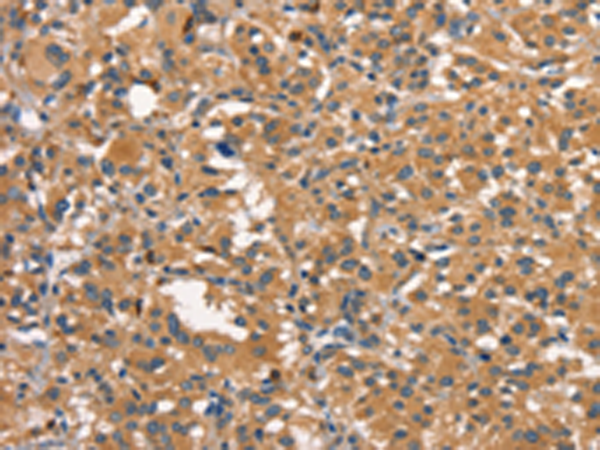

分类: 科研抗体货号: P04896别名: HGAL; GCAT2; GCET2应用: IHC反应种属: Human